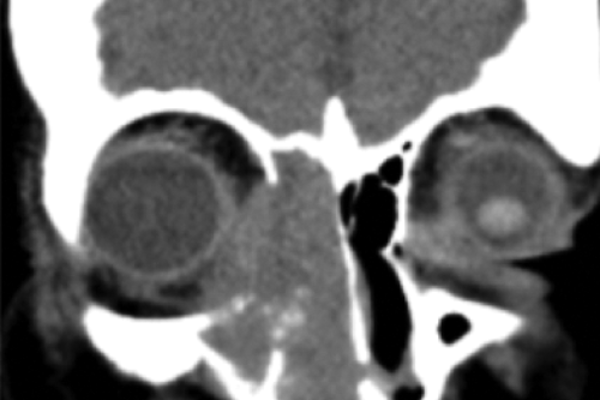

Chronic dacryocystitis?

S Shanmugalingam